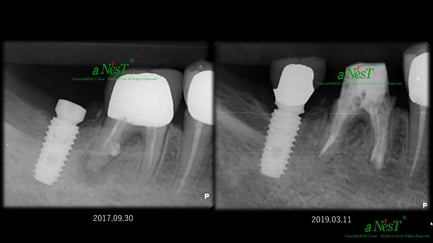

他院で抜歯と診断された症例です。友人の歯科医師の紹介で遠方から通院されました。初診時(左図)には、楔印で示すように、歯の根の先に黒い影が明瞭に写っています。が治療開始から8ケ月後(右図)では、黒い影は消えたり縮小しています。

歯の根の先の黒い影も消え(左図)、(手前は完全に消えていないが、完全な縮小傾向と症状がない)たので、クラウンを装着するための型採りをします。

右図の楔印は破折線です。破折線は特殊な方法で修復しています。

治療期間:約1年

治療回数:10回(1回/月)

治療費:29万円(根管治療+支台築造+セラミックス・クラウン)※毎回の処置料は別途

治療のリスク:他院では再治療ができないこと。

※リスクはどのような治療にも必ずあること。